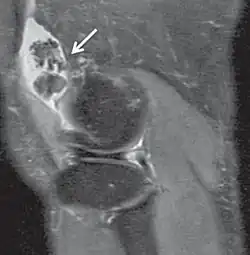

| Proton density weighted | PD | Long TR (to reduce T1) and short TE (to minimize T2).[7] | Joint disease and injury.[8]

Proton density

Proton density (PD)- weighted images are created by having a long repetition time (TR) and a short echo time (TE).[36] On images of the brain, this sequence has a more pronounced distinction between grey matter (bright) and white matter (darker grey), but with little contrast between brain and CSF.[36] It is very useful for the detection of arthropathy and injury.[37]